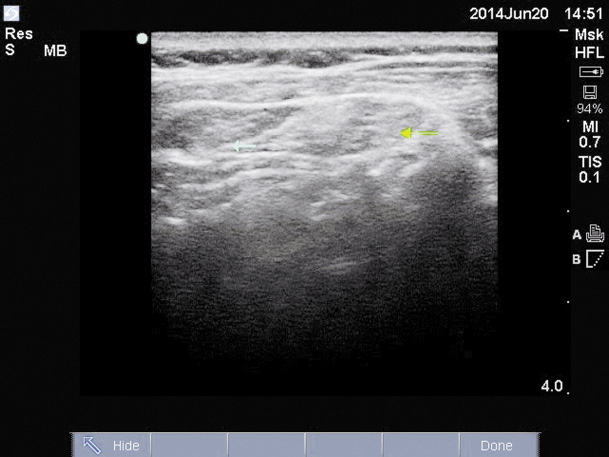

Le muscle splénius capitis est impliqué dans de nombreuses formes de TS (torticolis rotatoire, latérocolis et/ou rétrocolis). Il est accessible à la palpation dans le fond de l’angle formé par les muscles SCM en avant et trapèze en arrière. L’échographie constitue une méthode de choix indolore ; elle permet de préciser sa localisation et diriger l’injection de BoNT (fig. 2).

![]() |

| Figure 2 Injection de toxine botulique dans le muscle splénius capitis |